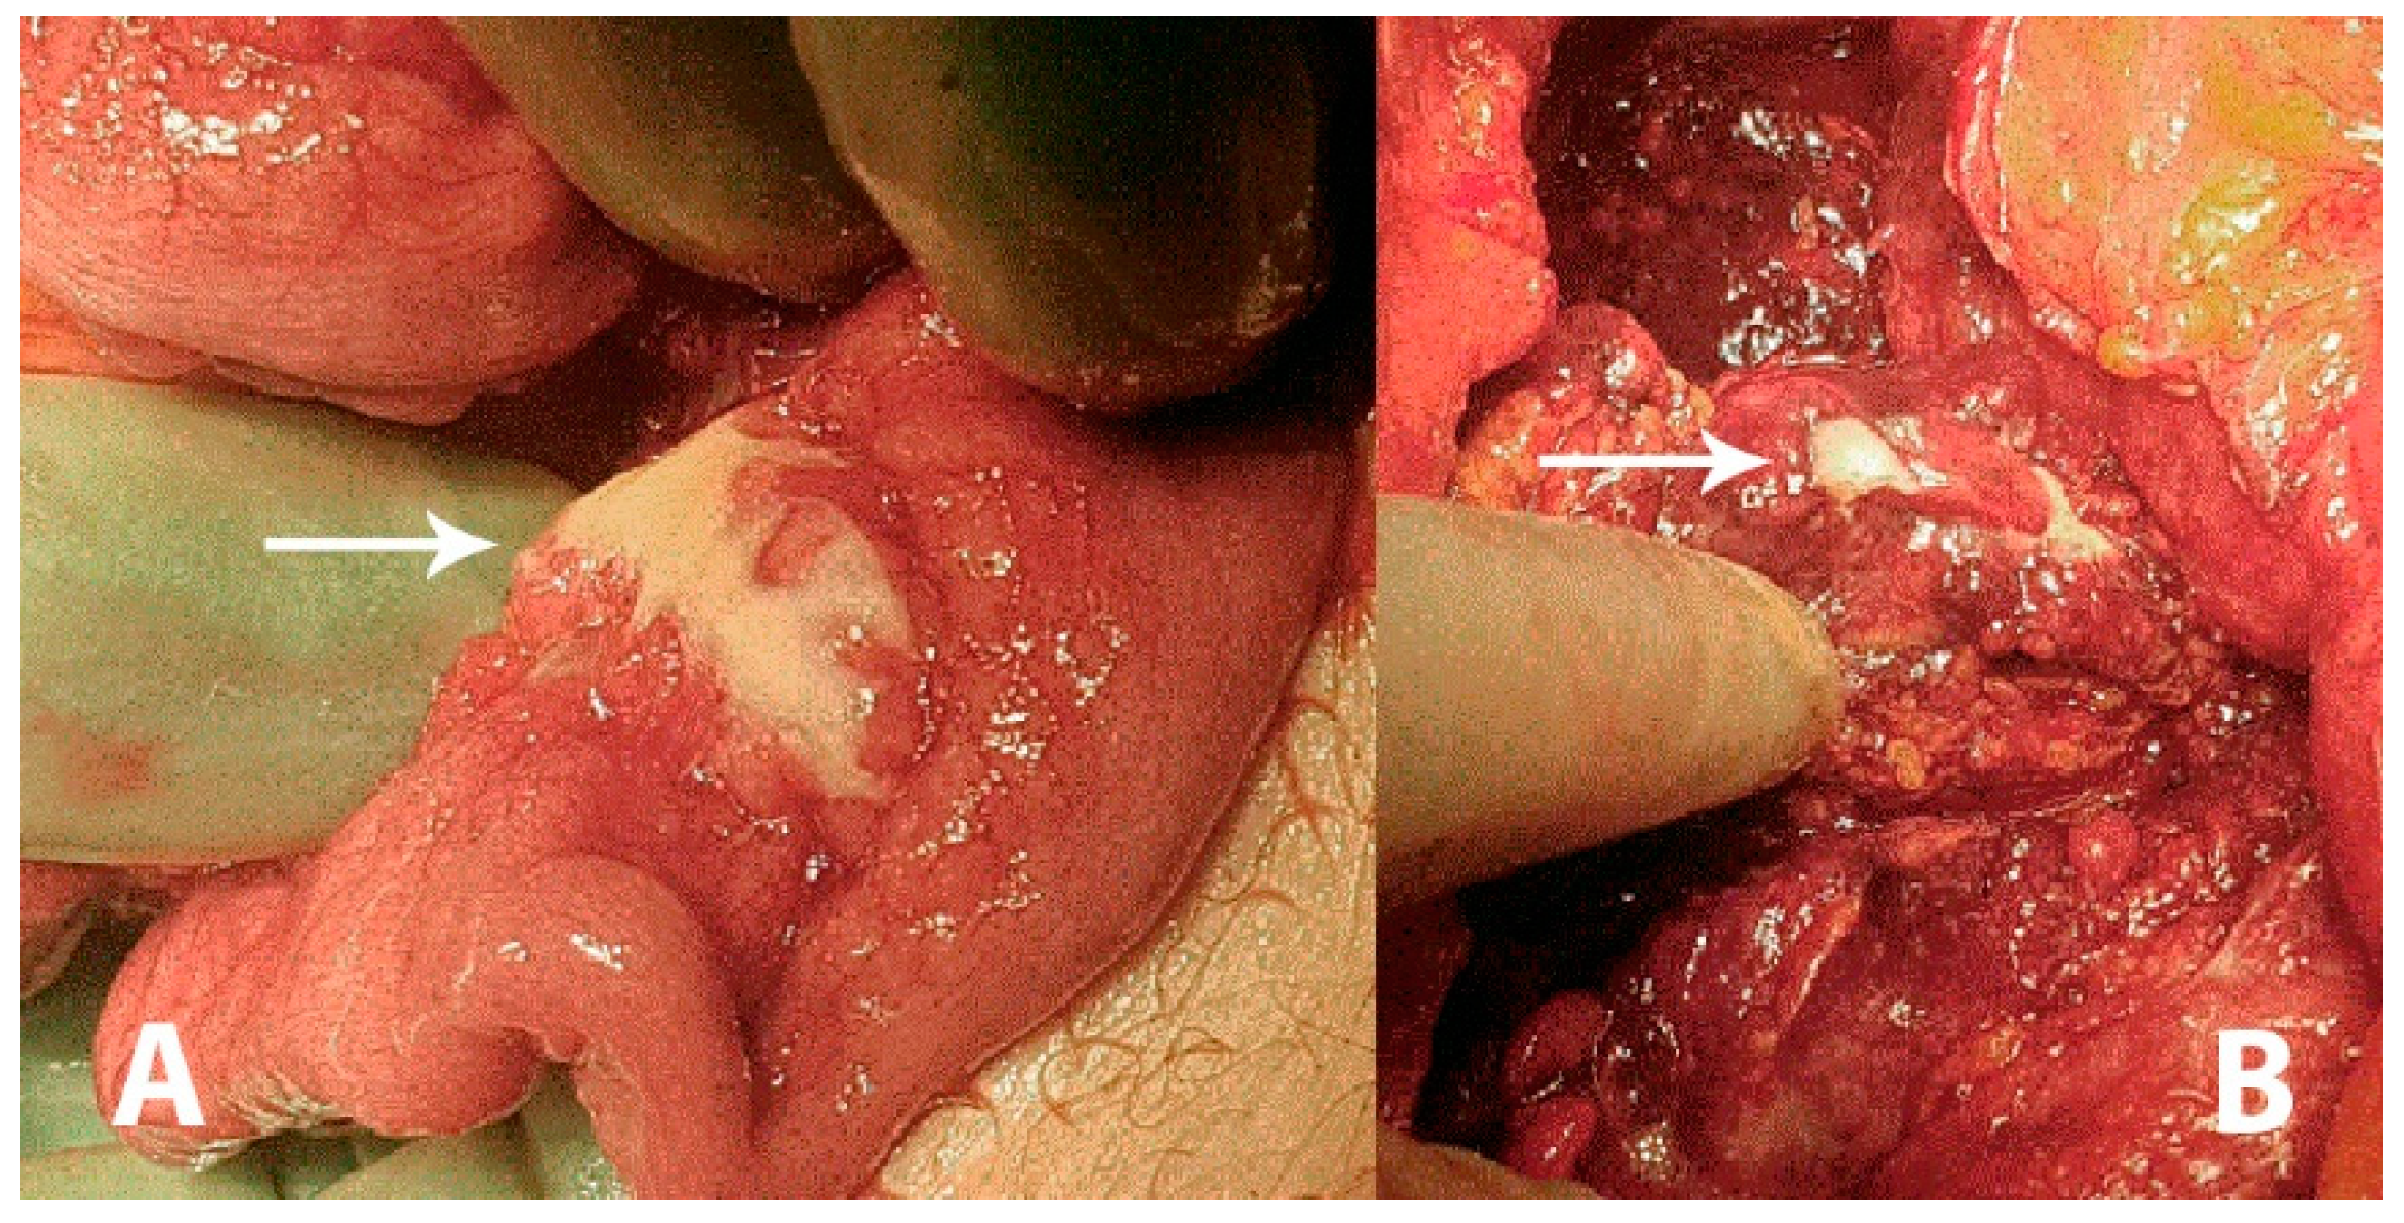

A 43-year-old previously healthy male was admitted to the surgical unit by his general practitioner with suspicions of acute diverticulitis. The patient complained of constant pain in the epigastric region and under the right and left rib curvature for the previous week upon admission. The pain was intensified when bending forwards and accompanied by an unspecific feeling of fatigue. The patient reported similar symptoms three weeks prior to admission, which remitted spontaneously. Any systemic symptoms of fever, unintended weight loss or night sweats were denied. At admission, the patient had a slight tachycardia; all other vital parameters were normal. Initial laboratory data came out with an elevated C-reactive protein (CRP; 176 mg/L) and a slightly elevated total leukocyte count (9.8 × 109/L). Hepatic and renal biochemical markers were within normal ranges. On physical examination the abdomen was described as tender in the upper quadrants and around the umbilicus but without peritoneal reaction. On suspicion of an intraabdominal abscess, a computed tomography (CT) scan was performed showing free liquid surrounding the liver and the spleen as well as in the small pelvis. There was no free air. However, the upper abdomen was seen with a diffuse reaction in the fatty tissue around the pylorus and ventricle. Radiologically, a perforated ulcer was suspected. The patient underwent a diagnostic laparoscopy, revealing peritonitis in all quadrants and three liters of free fluid. There were no signs of feces, pus or bile. The greater omentum was adherent in a conglomerate consisting of the duodenum, ventricle, pancreas and transverse colon. It was not possible to get a sufficient overview of the structures laparoscopically and the procedure was converted to an explorative laparotomy revealing reactive, stearin-like changes spread in the peritoneal cavity ((A,B), white arrows). The conglomerate was dissected and the posterior part of the ventricle was inspected, revealing no ulcers. The duodenum was mobilized by the Kocher maneuver, also revealing no ulcers or perforation. Perioperatively, an esophago-gastro-duodenoscopy was performed, revealing no ulcerations or pathology. A piece of the omentum was removed for histopathological examination and an intraabdominal drain was placed before ending the procedure. The findings were suspected to be caused by pancreatitis. The postoperative course was uneventful, the drain was removed after seven days and the patient was discharged after eight days with a plan of outpatient follow-up. On postoperative day 17 he was readmitted for drainage of 3.5 L ascites, which had recollected. The pancreas was without signs of pancreatitis on a triple-phase CT. Diagnostic ultrasound described no gallstones.